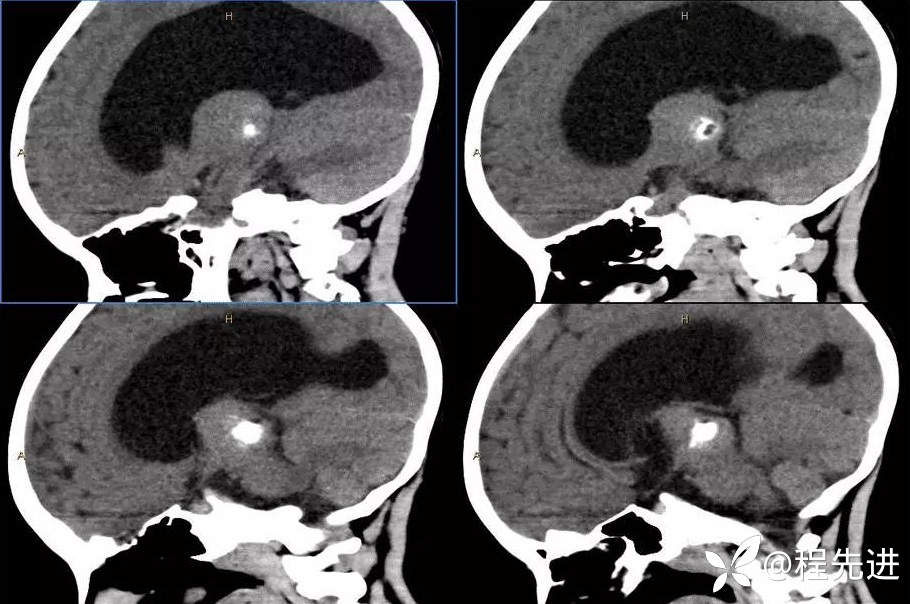

CT